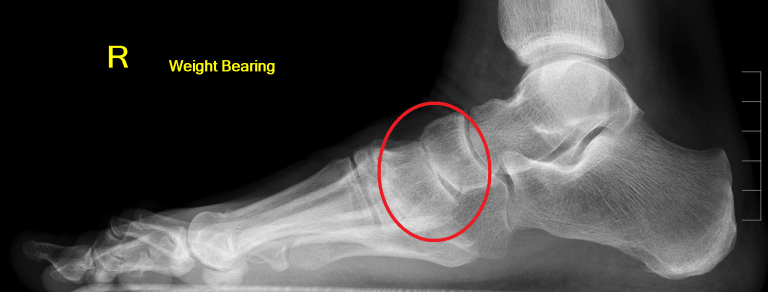

Midfoot arthritis is where there is a reduction in one or many of joint spaces within the midfoot.

Moderate arthritis of the joint of the navicular and medial cuneiform

Normal left foot